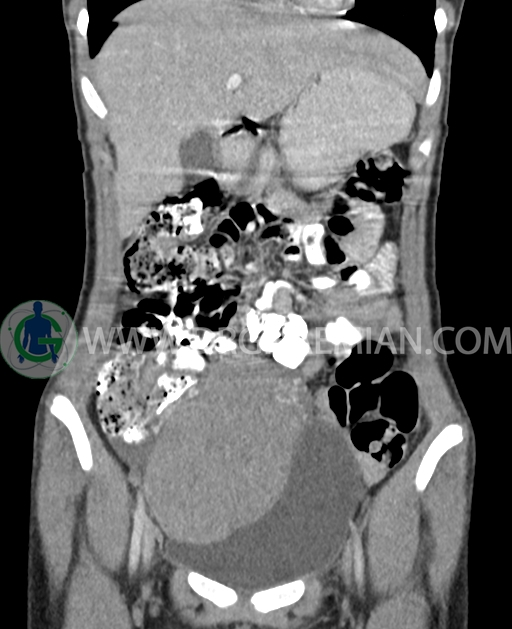

سی تی اسکن شکم و لگن از تشعشعات برای ایجاد تصاویر عرضی مقطعی از نایحه شکم و بین استخوان های لگن استفاده می کند. در این کیس تومور سلول زایا به ابعاد mm 125 x 112 x 80 دیده می شود.

در سی تی اسکن اسپیرال شکم و لگن با کنتراست خوراکی و وریدی (مولتی دیدکتور 16 با مقاطع ظریف و بازسازی های ساژیتال و کرونال) :

توده هیپردنس لوبوله بزرگ به ابعاد 125x112x80mm حاوی نواحی سیستیک داخلی و enhancement قابل توجه پریفرال همراه با آسیت متوسط در فضای شکم و لگن با احتمال بیشتر با منشا از تخمدان راست، درون لگن دیده می شود که در درجه اول مطرح کننده germ cell tumor می باشد .